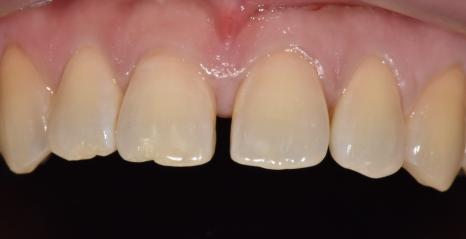

라미네이트를 통해

앞니 4개의 균형을 맞추고 나니,

단 며칠 만에 인상이 훨씬 단정해지셨습니다.

260108 / 260124